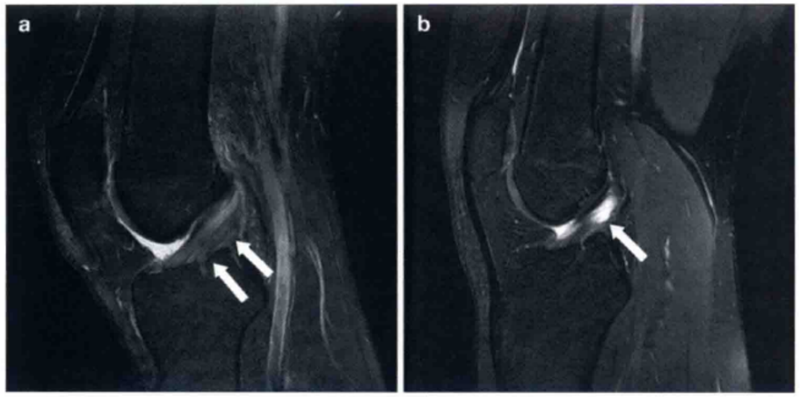

图9 a和b显示的为矢状位质子加权像和T2上PCL损伤的图像(箭头)。PCL变厚、水肿,但不是完全的断裂